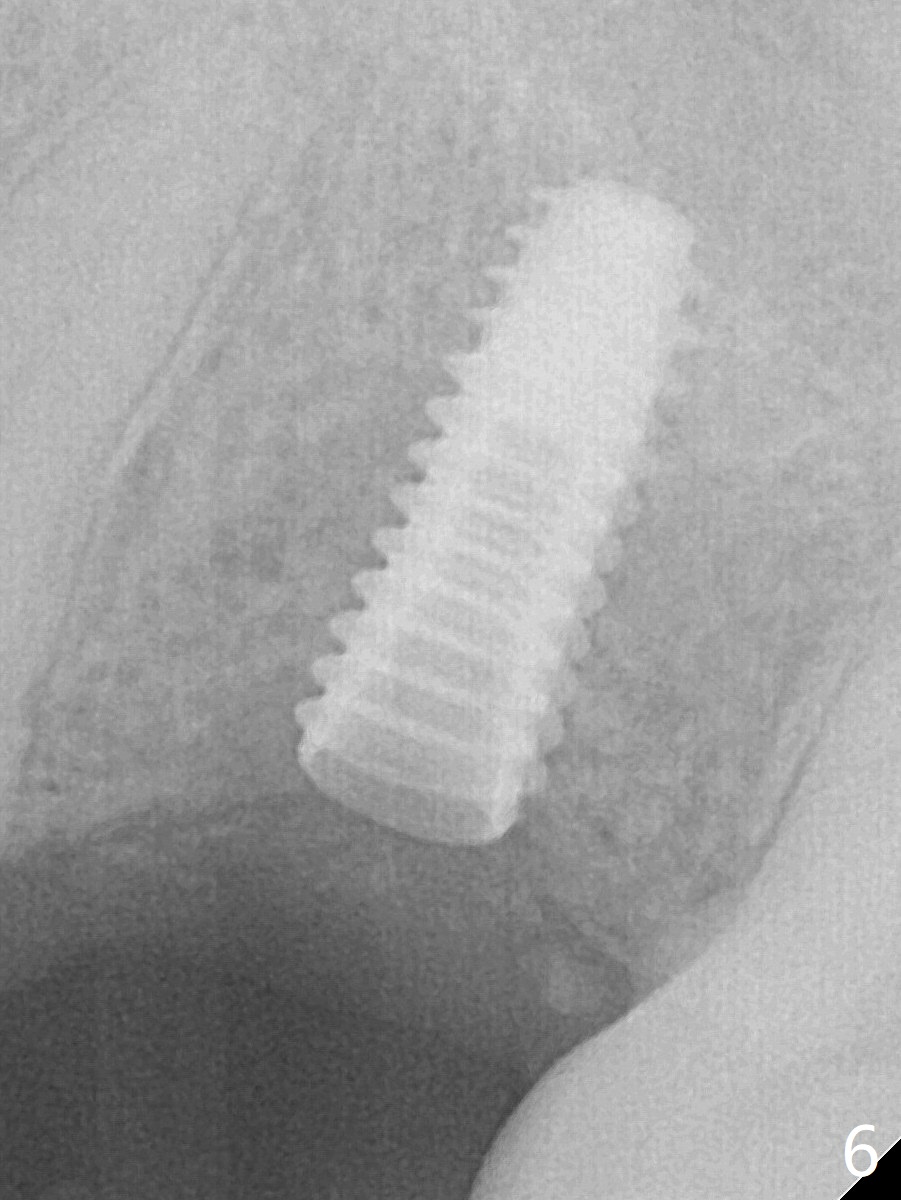

A 3.7 mm drill has to be used for 12 mm before placement of a 4.5x11.5 mm implant with >35 Ncm (Fig.5). A 5.5x5(3) mm abutment is placed with allograft (<) placed around the implant. Following suturing, periodontal dressing is applied around the implant. The abutment dislodges 3 months postop (Fig.6). Crown is delivered 3 weeks later. The abutment screw is retightened ~ 2 months later.